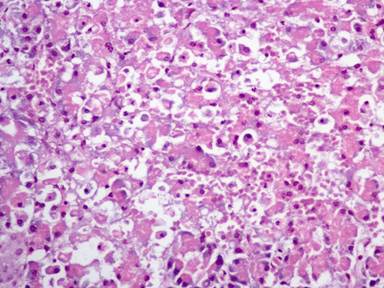

The results of the histopathological evaluation are presented in Table 1. No statistically significant differences were noted concerning edema (P=0.563), hemorrhage (P=0.241), leukocyte infiltration (P=0.256), acinar necrosis (P=0.231) and vacuolization (P=0.438) between the two groups. Figures 1 and 2 present representative pathological cases.

Figure 1. Effects of acute ischemia and reperfusion on pancreatic histology. This field is characterized by the complete distortion of the pancreatic parenchyma caused by the presence of conspicuous hemorrhage, moderate interlobular and intralobular edema and some small necrotic foci (approx. 20%). H&E x400. |